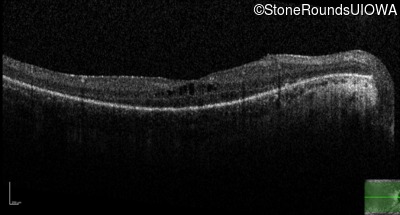

Optical Coherence Tomography - Right - 20/40

Exemplar / OCT Stack